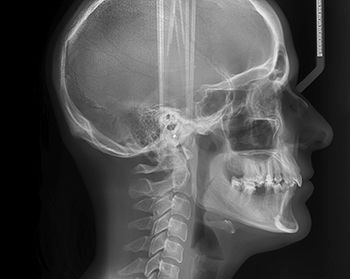

Основой диагностики патологий носоглотки служит рентген околоносовых пазух – исследование, основанное на проникающей способности жесткого ионизирующего излучения.

Проходя через костно-хрящевые структуры и мягкие ткани, рентгеновские лучи образуют специфический рисунок на фотопленке или чувствительном экране цифрового аппарата.

Изображение отражает особенности строения носоглоточных и лобных полостей, носовых ходов и других анатомических элементов исследуемой области.

На основании полученных снимков ЛОР-врач ставит диагноз и определяет наилучшую схему лечения.

• Меняя положения головы, выполняют снимки в четырех проекциях – боковой, подбородочно-черепной, задне-передней и позиции Уотерса.

Снимки, сделанные в нескольких проекциях, создают наиболее полную картину патологических изменений исследуемой области.

Рентгеновское исследование пазух носа – это безболезненная процедура, для выполнения которой необходимо посетить специальный кабинет клиники, оснащенный соответствующим оборудованием. Обследование назначает лечащий ЛОР-врач. Снимки обязательно выполняются в нескольких проекциях, чтобы лучше выявить патологические процессы или травматические повреждения. При проведении диагностики рентгенолог выбирает позиции, позволяющие наиболее полно отобразить особенности внутреннего строения носо-лобной области.